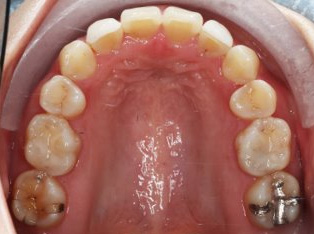

乱ぐい歯、でこぼこがとても酷い状態になります。歯が前後的に重なってしまっている、八重歯になっているなどがこのジャンルに入ります。

顎の大きさと歯の大きさのギャップが大きく、時には歯を抜かないと矯正治療ができない場合もあります。当院では治療期間が長くなるが抜かない治療方針など、一つの治療プランだけでなく、さまざまな可能性の治療方針を説明させて頂くよう心掛けております。こういった考え方はインフォームド・チョイスと言われ近年大切にされている考え方と言われております。

治療前

治療終了前